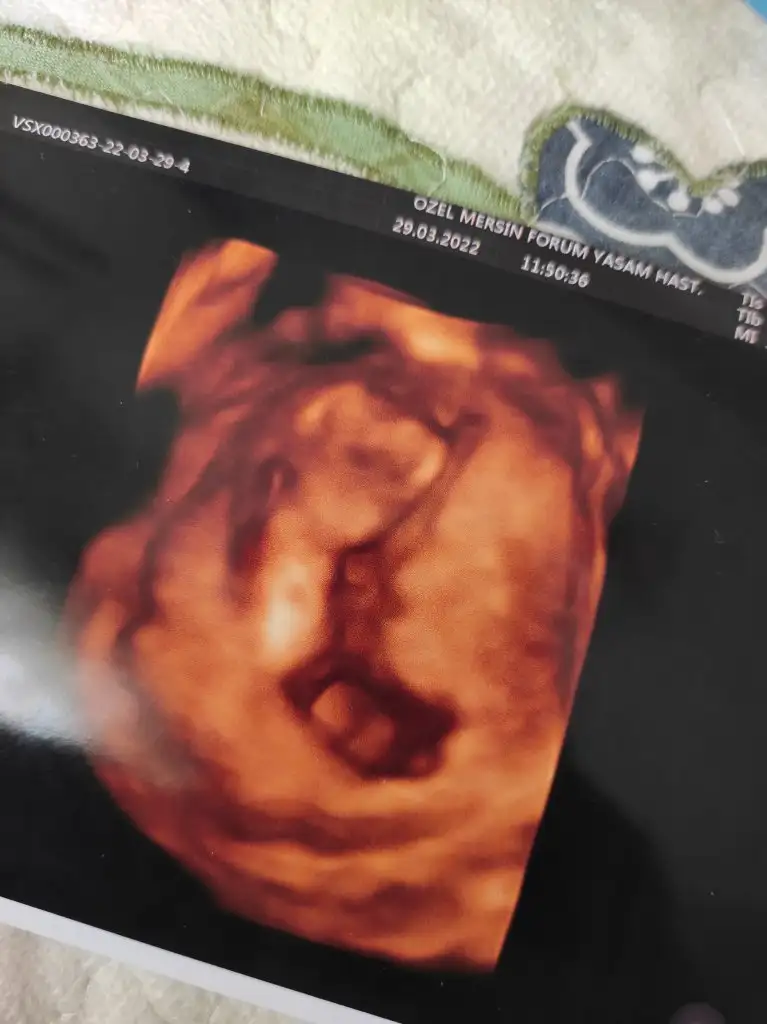

Merhaba :) bana 6.haftada erkek demiştiniz. Doktor da 12+3te erkek gibi dedi, tekrar bakabilir misiniz :)Hala kız gibi duruyorhadi bakalım inşallah kalbinden ne geçiyorsa o olur

O pipi gibi ama altındaki paralel olan şey neterzi söküğünü dikemez hesabı ben bir şey diyemiyorum bakın sizce bu yatay duran pipimi

Merhaba :) bana 6.haftada erkek demiştiniz. Doktor da 12+3te erkek gibi dedi, tekrar bakabilir misiniz :)